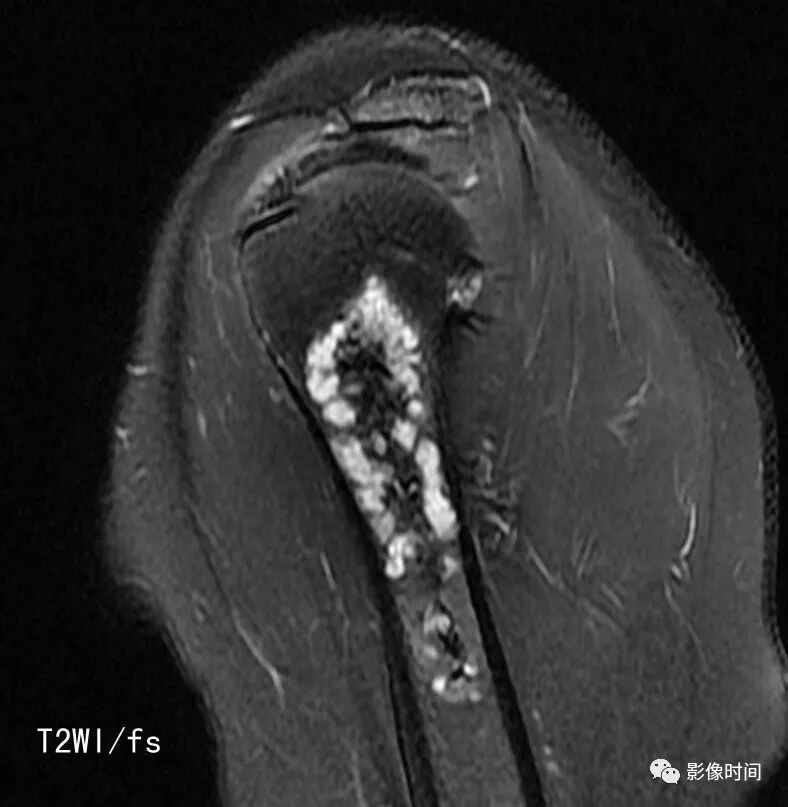

由于瘤软骨多由富含水分及粘多糖的透明软骨构成,故 T1WI 呈偏低信号,T2WI 或 PDWI 呈明显高信号,被低信号的纤维间隔分开呈分叶状(图 24、图 25a-b),增强扫描多呈不均匀分隔状强化(图 25c),主要是纤维间隔强化,瘤软骨强化不明显之故。

图 24  瘤软骨:内生软骨瘤

图 25  瘤软骨:内生软骨瘤